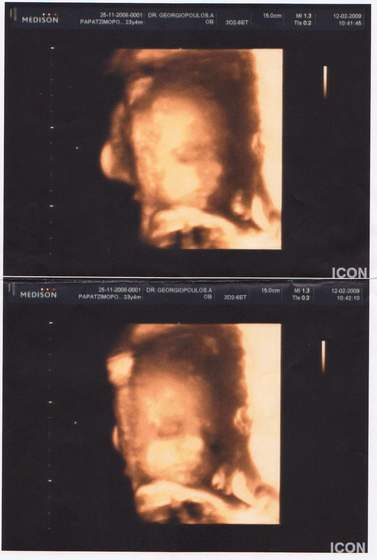

)wklejam kilka z nich...hehehe...